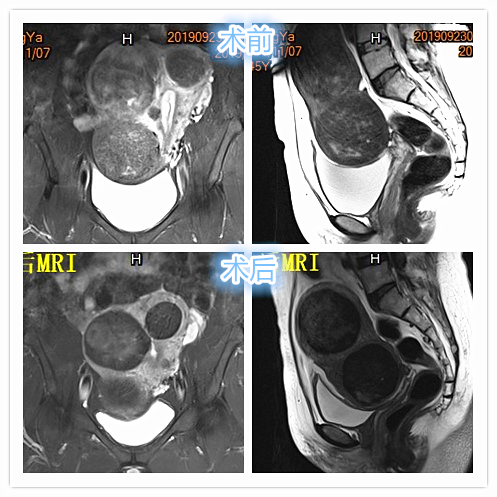

- MRI显示多发子巨大宫肌瘤,压迫膀胱。

- 术后3个月复查MRI显示多发肌瘤明显坏死、缩小。相关症状已基本消失。

术后3个月复查MRI